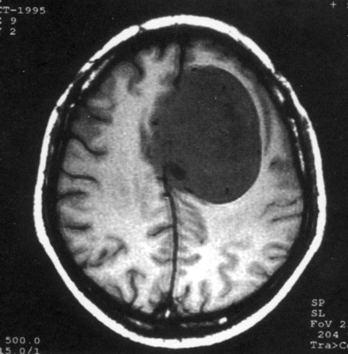

问题 病历摘要:??患者,男,40岁。发作性左下肢抽搐1年余,每次发作3~5分,每周发作1~2次。每次发作后感左下肢乏力,约半日后可自行恢复。既往身体健康。体检:神清,头顶部偏右有局限性骨性隆起(1.5×1.5cm),左鼻唇沟稍浅,伸舌居中。感觉、运动无明显异常。左浅反射减退,左下肢腱反射稍亢进,左Babinski征(-)。 可选择下列哪些检查帮助诊断